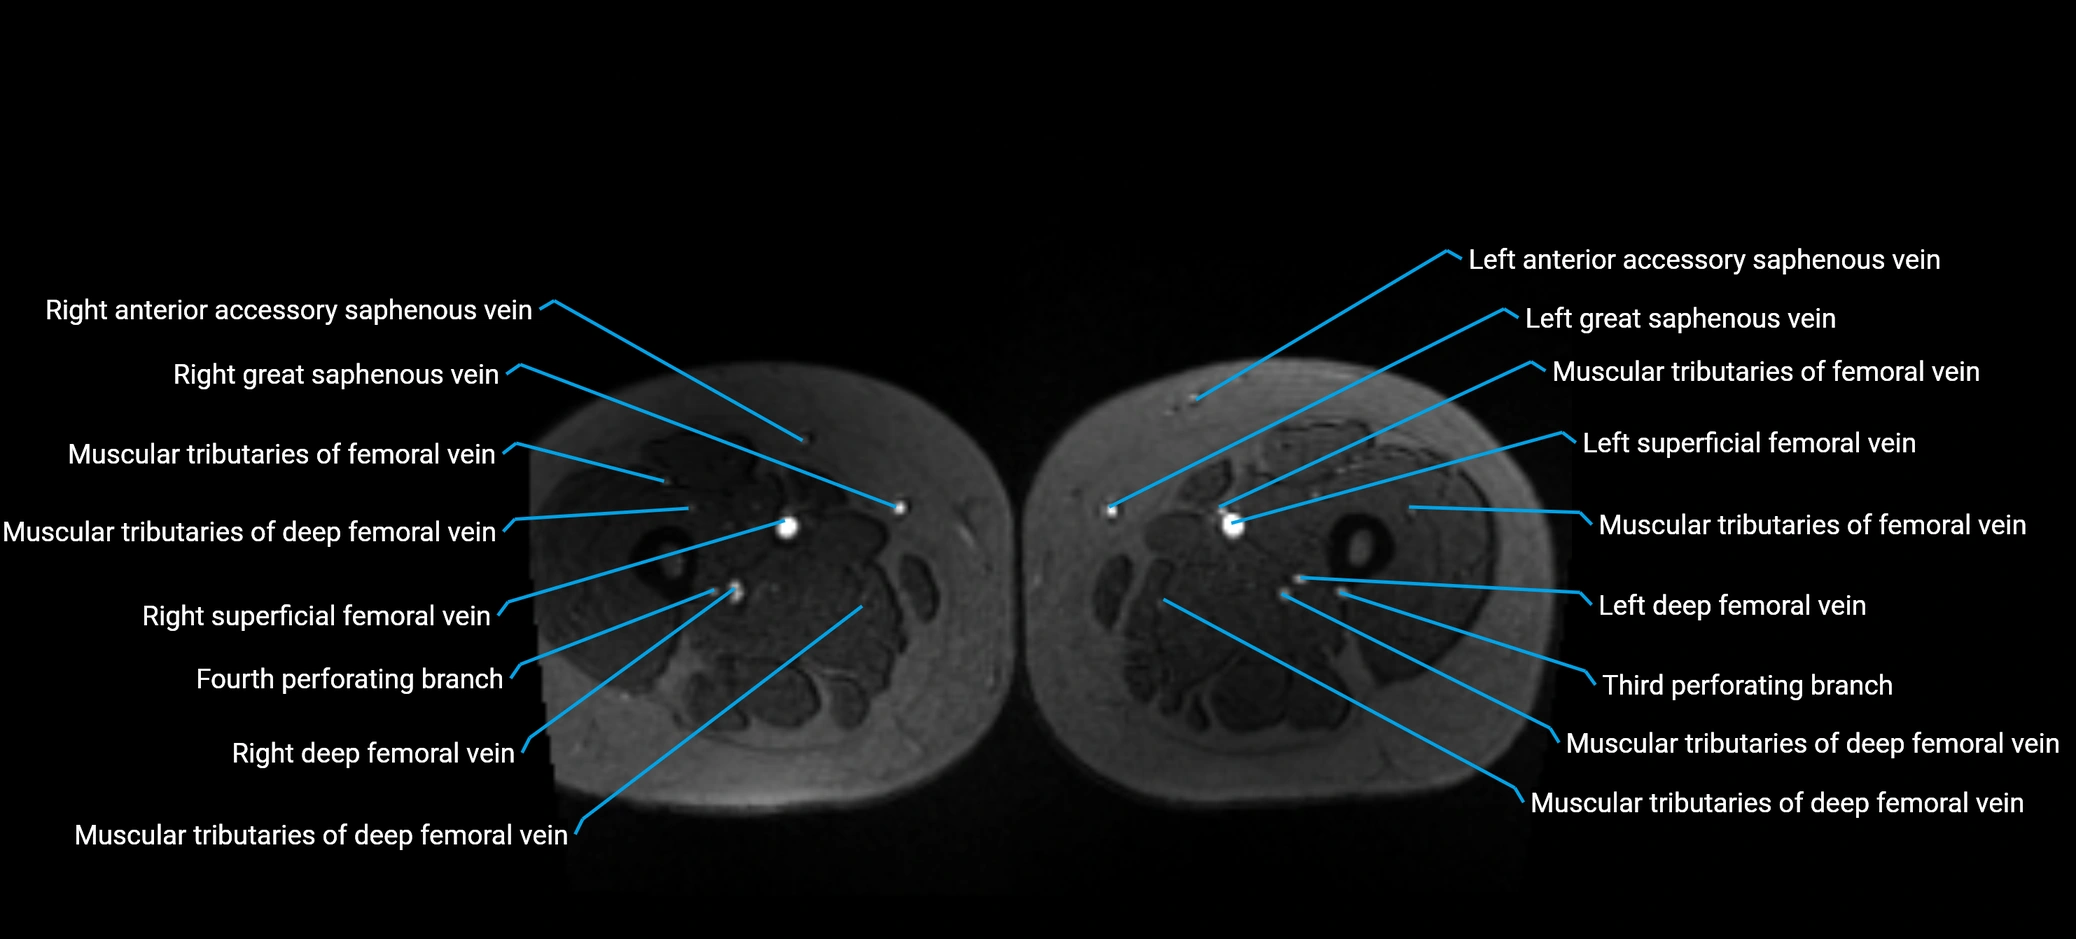

MRI image

image